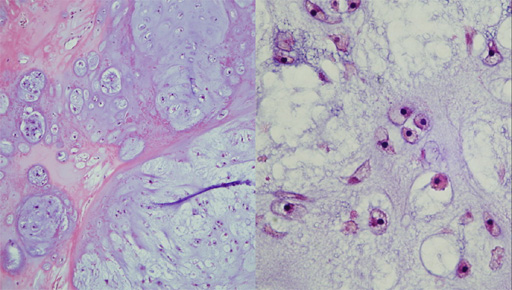

肋骨や横隔膜を巻き込む60×60×35mmの分葉状の腫瘤で、割面はゼラチン状で、嚢胞化や出血を含む。

主に軟骨形成を示す腫瘍で、myxoidな変性を含む。核異型は目立たないが、細胞密度がやや高い部分を含む。。